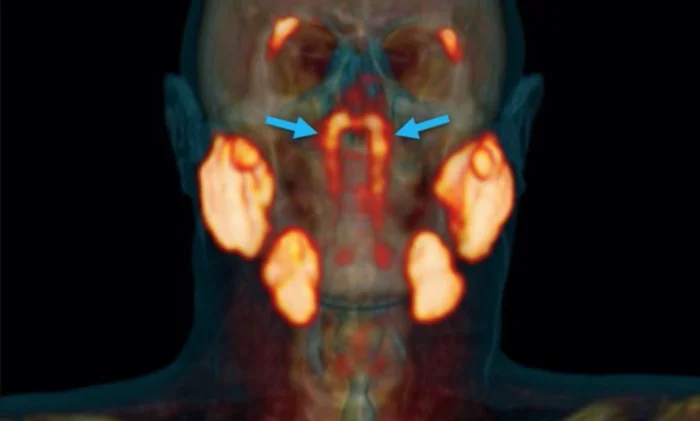

Совсем недавно голландские исследователи сделали неожиданное анатомическое открытие, обнаружив новый набор слюнных желез, расположенных в задней части носоглотки.

При этом этот новый набор желез, расположенных точно за носом и над нёбом, недалеко от центра человеческой головы, относится к первой категории. Врачи назвали их «трубчатыми железами» в связи с их анатомическим расположением (над основанием хрящевой части слуховой трубы).

Открытие этих трубчатых желез не единичный случай. Фактически, они наблюдались на снимках ПЭТ около 100 пациентов, обследованных во время исследования. Их также опознали на двух трупах — мужчины и женщины.

Как мы могли упустить их все это время? Сложно сказать. Исследователи отмечают, что структуры, расположенные под основанием черепа, не очень доступны. По их словам, их было бы даже невозможно отличить никакими средствами, кроме новых методов визуализации ПЭТ-КТ. Также возможно, что они были замечены раньше, но в конечном итоге были перепутаны с другими наборами желез.